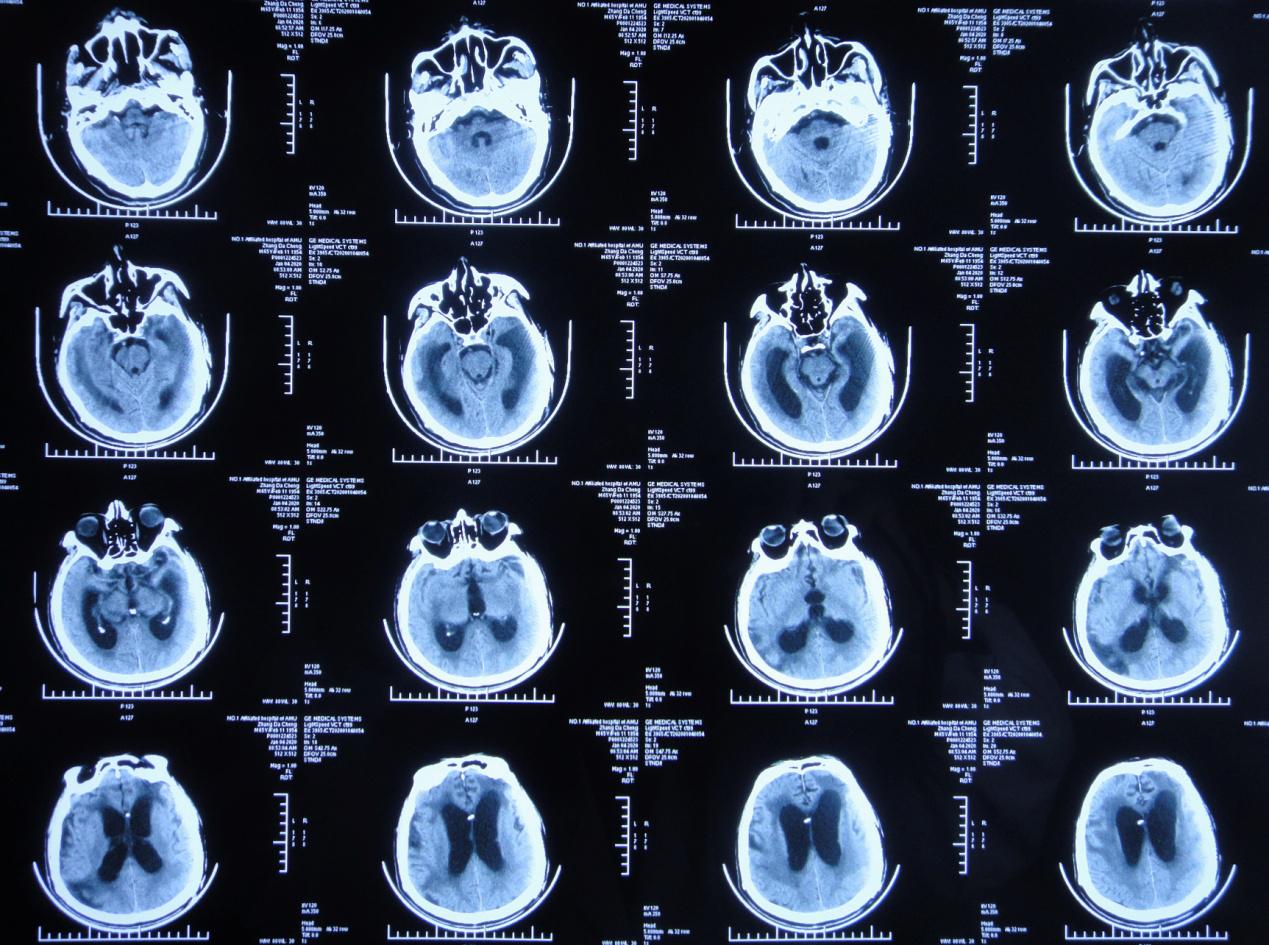

左颞叶血肿清除+去骨瓣减压术后第45天,即2019年8月24日,复查头颅CT( 图-3 )示颅脑术后改变,脑室基本“正常”,脑室周围稍水肿。

图-3: 2019年8月24日头颅CT

左颞叶血肿清除+去骨瓣减压术后第52天,即2019年8月31日,复查头颅CT( 图-4 )示脑室较前无明显变化,脑室周围仍稍水肿。

图-4: 2019年8月31日头颅CT